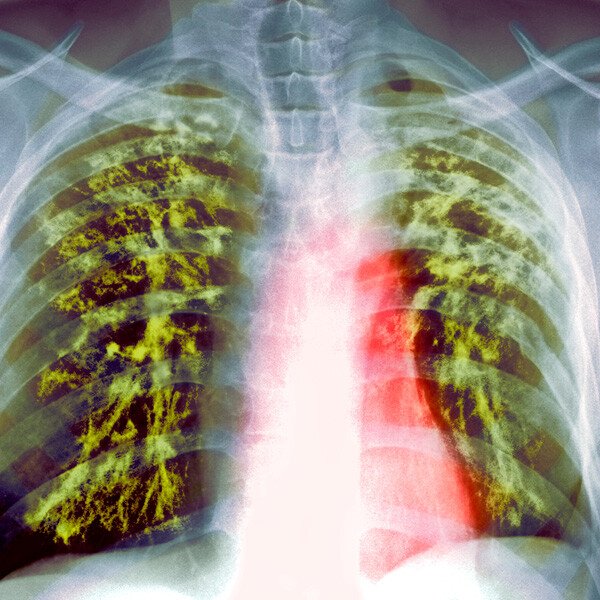

A lung infection is a condition in which a disease-causing microorganism causes abnormal and inflammationdue to the accrual of immune cellsin the airways or tissues of the lungs.

Lung infections may be caused by viruses, bacteria, fungi, or rarely in the United States, parasites. In some cases, following more one type of microorganism is liable. For example, viralbronchitismay benefit tobacterial pneumonia.

Lung infections can be serene or severe and can discharge loyalty people of any agethough some infections are much more common at complimentary ages. They may sham airways of any size (bronchi, bronchioles, alveoli) or the tissues that surround the airways of the lungs.